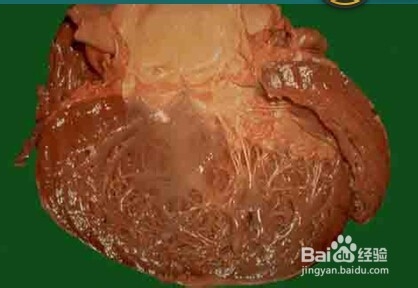

3、三:扩张型心肌病的实物图。